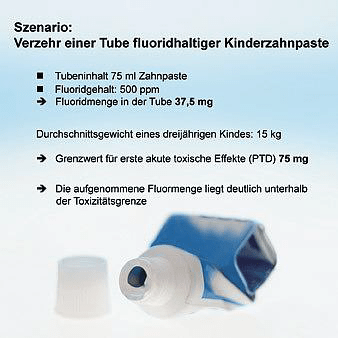

Abbildung 1: Berechnungsbeispiel zur akuten Toxizität von Fluorid nach Verzehr einer Tube Kinderzahnpaste durch ein dreijähriges Kind. © Schiffner

Prinzipiell kann Fluorid zur Kariesprophylaxe lokal auf die Zahnoberfläche aufgetragen werden (zum Beispiel mittels Zahnpaste) oder systemisch, wie über Trinkwasser oder Fluoridtabletten verabreicht werden. Bei der systemischen Anwendung können während der Zahnentwicklung aus dem im Plasma auf 0,01 bis 0,025 ppm verdünnten Fluorid geringe Anteile in den sich entwickelnden Zahnschmelz eingebaut werden. Bei der lokalen Fluoridanwendung an den bereits in der Mundhöhle vorhandenen Zahnflächen können hingegen deutlich höhere Fluoridkonzentrationen wirksam werden. Die karieshemmende Wirkung der Fluorid- anwendung beruht auf dessen lokal an der Zahnoberfläche eintretenden Effekten [Lussi et al., 2012]. Daher wird der lokalen Fluoridapplikation eindeutig der Vorzug gegeben [DGZMK, 2013]. Der Erfolg sogenannter systemischer Fluoridanwendungen ist ebenfalls auf den lokalen Kontakt der entsprechenden Fluorid-Vehikel (Kochsalz, Wasser, Tabletten) mit der Zahnoberfläche zurückzuführen. Die untere toxische Grenze von Fluorid (Probably Toxic Dose PTD) wird mit 5 mg Fluorid pro kg Körpergewicht angegeben [Whitford, 1992 und 2011]. Symptome können Übelkeit, Schwindel und Erbrechen sein. Als Gegenmittel wird die orale Gabe von Kalzium beziehungsweise aus Praktikabilitätsgründen von Milch angegeben, eventuell nach vorherigem Veranlassen des Erbrechens [Whitford, 2011]. Über den Erfolg oder die Notwendigkeit dieser Maßnahmen besteht jedoch keine Evidenz, da die Empfehlungen theoretisch abgeleitet und nicht in hinreichender Anzahl praktisch umgesetzt werden müssen. Dies kann ein Berechnungsbeispiel zur Fluoridbelastung nach Verzehr einer Tube Kinderzahnpaste durch ein dreijähriges Kind veranschaulichen (Abbildung 1).

Es ist erkennbar, dass in diesem Szenario keine toxikologisch relevanten Fluoridmengen aufgenommen werden. Sofern das dreijährige Kleinkind eine gesamte Tube Erwachsenenzahnpaste verzehren sollte, wird die PTD mit den erwähnten unangenehmen Symptomen überschritten. Von ernsthaften Konsequenzen wäre aber auch dieses Szenario weit entfernt.